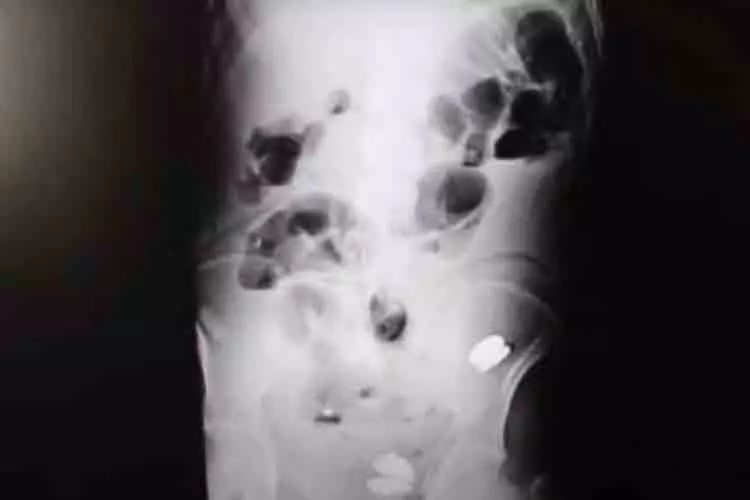

തുർക്കിയിൽ 35കാരന്റെ വയറ്റിൽനിന്നും 233 നാണയങ്ങൾ, നഖങ്ങൾ, ബാറ്ററികൾ, ഗ്ലാസ് കഷ്ണങ്ങൾ എന്നിവ കണ്ടെടുത്ത് ഡോക്ടർമാർ. വയറുവേദനയെ തുടർന്ന് ഡോക്ടറെ സമീപിച്ച 35 കാരന്റെ വയറ്റിൽനിന്നാണ് നാണയങ്ങളും മറ്റും കണ്ടെടുത്തത്. അൾട്രാസൗണ്ട്, എക്സ്-റേ എന്നിവ ഉപയോഗിച്ച് എൻഡോസ്കോപ്പി നടത്തിയാണ് ഡോക്ടർമാർ ഇയാളുടെ വയറ്റിൽനിന്നും നാണയങ്ങളുൾപ്പെടെയുള്ളവ കണ്ടെത്തിയത്. ഗൾഫ് ടുഡേയാണ് ഇക്കാര്യം റിപ്പോർട്ട് ചെയ്തത്.

ലിറ നാണയങ്ങൾക്ക് പുറമെ മാഗ്നറ്റുകളും സ്ക്രൂകളും യുവാവിന്റെ വയറ്റിൽനിന്നും ഡോക്ടർമാർ കണ്ടെടുത്തു. ''ശസ്ത്രക്രിയയ്ക്കിടെ, വൻകുടലിൽ രണ്ട് ലോഹക്കഷണങ്ങളും വ്യത്യസ്ത വലിപ്പത്തിലുള്ള രണ്ട് കല്ലുകളും ഒന്നോ രണ്ടോ നഖങ്ങളും ഞങ്ങൾ കണ്ടു, ഞങ്ങൾ അദ്ദേഹത്തിന്റെ വയർ പൂർണമായും ശുദ്ധീകരിച്ചു''- ശസ്ത്രക്രിയാ വിദഗ്ധരിൽ ഒരാളായ ഡോ. ബെനിസി പറഞ്ഞു. കുട്ടിക്കാലത്ത് ചിലയാളുകൾ ഭക്ഷ്യ യോഗ്യമല്ലാത്ത പദാർത്ഥങ്ങൾ കഴിക്കാറുണ്ടെന്നും മാനസിക രോഗികളിലും ഇത്തരം അവസ്ഥകൾ കാണാമെന്നും സർജൻ കൂട്ടിച്ചേർത്തു. എന്നാൽ യുവാവിന്റെ വയറ്റിൽ എങ്ങനെയാണ് ഇത്തരം വസ്തുക്കൾ എത്തിയത് എന്നതിനെ പറ്റി റിപ്പോർട്ടുകൾ വ്യക്തമാക്കുന്നില്ല.